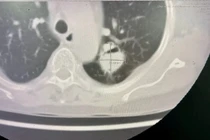

Bệnh viện Đa khoa tỉnh Quảng Ninh vừa thực hiện thành công ca cắt thùy phổi cho bệnh nhân nữ 65 tuổi mắc u nấm phổi phức tạp, chấm dứt tình trạng ho ra máu kéo dài.

Bệnh nhân Đ.T.L., trú tại Hưng Yên, có tiền sử bệnh phổi tắc nghẽn mạn tính, nhập viện trong tình trạng ho nhiều và ho ra máu tái diễn. Kết quả thăm khám, hội chẩn xác định bệnh nhân có u nấm phổi thùy trên phổi trái, nguy cơ chảy máu nặng nên được chỉ định phẫu thuật cắt thùy phổi.